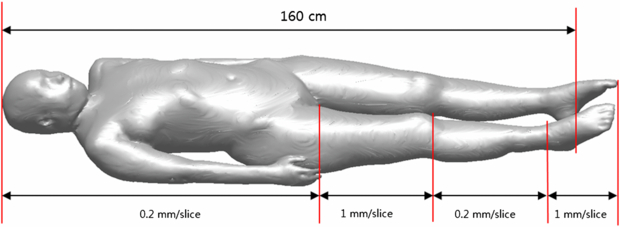

To develop a high-quality reference Korean female phantom, the cadaver (160 cm height, 52.35 kg weight, 26 years of age) was selected carefully in order to match as closely as possible the reference Korean female data (161 cm, 54 kg). Photographic images of the cadaver, fixed and frozen in an immobilization box, were taken in 0.2 mm intervals with a cryomicrotome; for the thighs and feet only, the interval was 1 mm as shown in figure 1. A total of 5901 images (pixel-resolution: 0.1 × 0.1 mm2), thus acquired, were saved as 24-bit color tag image file format files. High-resolution color images of this type, which provide very accurate anatomical information when compared with CT and MRI images, are essential for precise segmentation of organs and tissues. For bone-segmentation uses, 1 mm interval CT images also were obtained.

Figure 1. External form of female cadaver with indicated sectioning interval information.